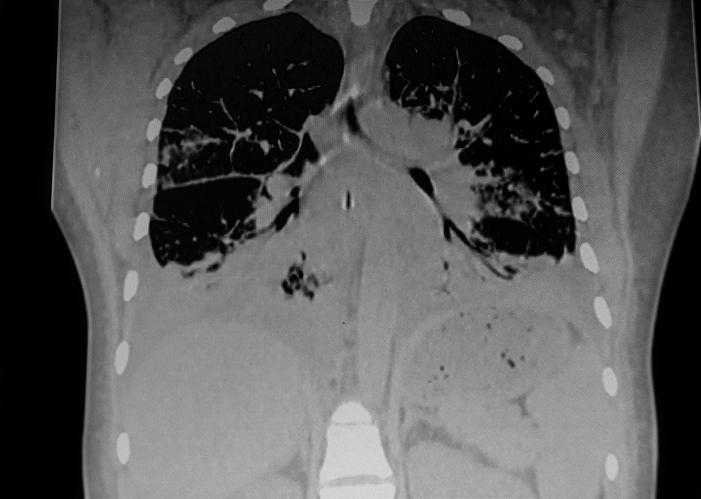

Lymphangioleiomyomatosis

Professor Simon Johnson, Director of the UK centres for Lymphangioleiomyomatosis (LAM) and Rare Cystic Lung Diseases based at the University of Nottingham, will co-lead the LifeArc centre.